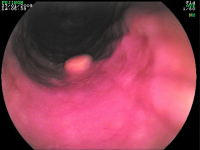

Tumor - Ileum

Abbildung 5: Neuroendokrines Karzinom im terminalen Ileum mit Vorwölbung der Ileozökalklappe.

Keywords:

Endoskopie

,

Gastroenterologie

Ileum

Tumor